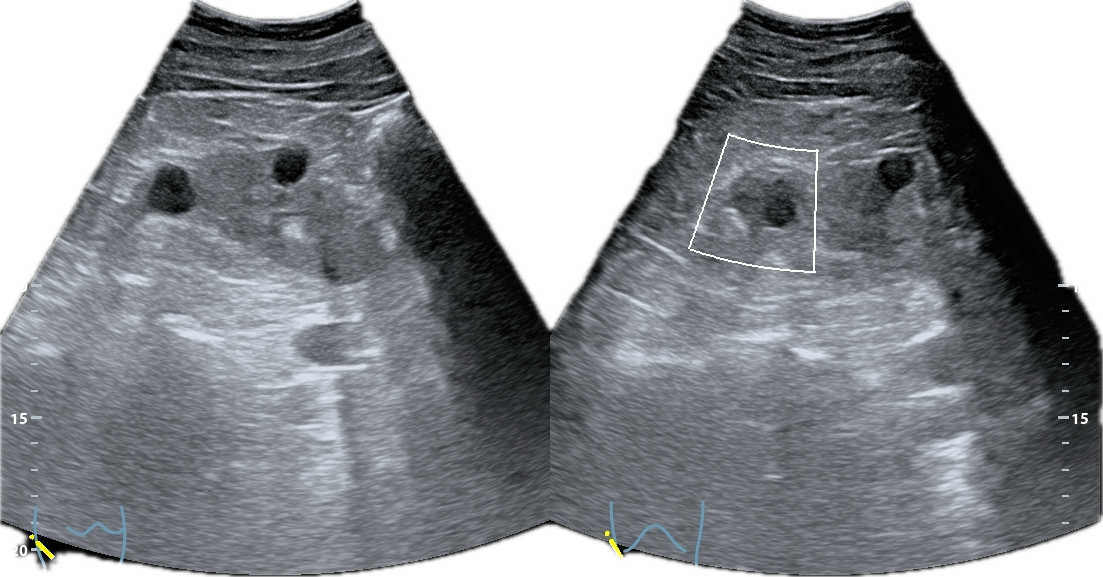

La ecografía abdominal muestra ambos riñones con múltiples quistes corticales y medulares, de diferentes diámetros, distribuidos de forma difusa.

El parénquima presenta un aspecto multiquístico que confiere una morfología global cribo forme, semejante visualmente a un «queso gruyere». No se observan litiasis, ni signos de obstrucción de la vía urinaria.

El quiste de mayor tamaño (aprox. 9 cm) se observa en riñón izquierdo; sin ecos internos, calcificaciones o sextos (categ BosniaK 2). En riñón derecho se aprecian múltiples quistes alguno de ellos con esto grueso en su interior, sin calcificaciones ni componentes sólidos en su interior (categ. BosniaK 2-3).